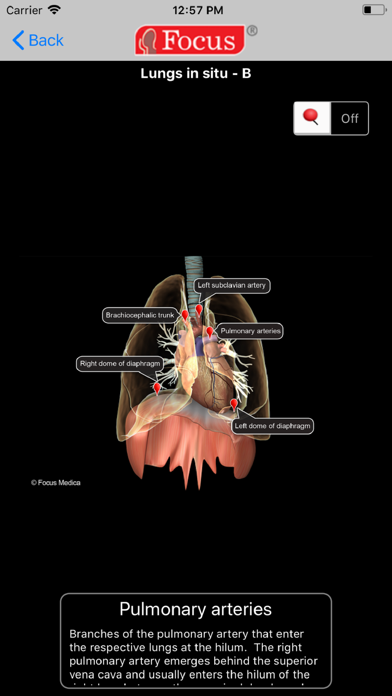

1. * A 3D animated, reference tool to recognize and comprehend anatomical positions, planes, dissection layers, and understand clinical manifestations of various medical conditions.

2. Extensive information accessible through valuable visual tools using 3D animations accompanied by audio and interactive images.

- A 3D animated, reference tool to recognize and comprehend anatomical positions, planes, dissection layers, and understand clinical manifestations of various medical conditions

- Includes Interactive images with detailed description for each label, enabled with user-paced on/off feature and zoom-in/out options